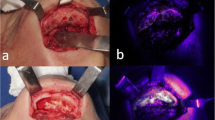

The first surgical intervention was performed after the above pretreatment of 12 weeks at ARI. All surgical procedures were performed under general anesthesia according to our standardized protocol [15]. The first molar teeth of the mandible and the maxilla were extracted unilaterally (Fig. 1) to determine whether any differences occurred between the upper and lower jaw. On the contralateral side, no teeth were extracted, which was therefore used as the control side. All tooth extractions were performed without incidences or complications, apart from some small root remnants.

The second surgical intervention was performed 8 weeks after the first surgical intervention and after a continuation of the antiresorptive treatment for another 8 weeks. All surgical procedures were performed under general anesthesia according to our standardized protocol [15]. Following in vivo sub-periosteal preparation of the MRONJ regions (and of the control side), detailed high-resolution photographic documentation was performed on macroscopic necrosis signs and on non-diseased areas (with and without illumination by fluorescence with the VELscope Vx system® (blue excitation light: spectrum 400–460 nm and a green filter with an emission open from 460 nm)) (Fig. 2). This enabled subsequent planned data analysis, correlating in vivo and in vitro macroscopic and histological results.

Macroscopic in vivo evaluation

No macroscopic clinical differences in fluorescence were seen between the auto-fluorescence and the tetracycline-fluorescence groups. Macroscopically viable bone was marked by green fluorescence and visualized intraoperatively with a VELscope Vx system®. In contrast, necrotic bone showed no or only pale fluorescence in both groups. Because mostly early stages of MRONJ were evaluated, a new aspect was serendipitously added to the evaluation, since early stages have not previously been described by using fluorescence, either preclinically or clinically.